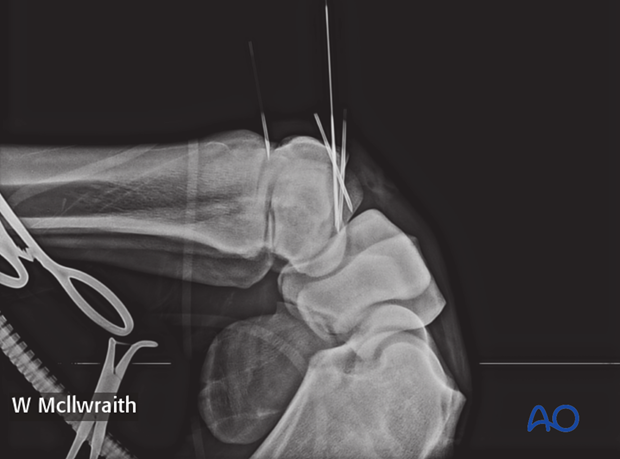

A flexed LM and ...

…skyline radiographinc views are taken to provide the proximal-distal location of the lag screw.

Based on the radiographs a stab incision is placed over the dorsal aspect of the third carpal bone half way between the spinal needle and the needle in the carpometacarpal joint.

The glide hole is drilled across the fragment until it enters the fracture line (the distance is predetermined by measurement by the radiographs).

The drill depth can be verified using an intraoperative radiograph.